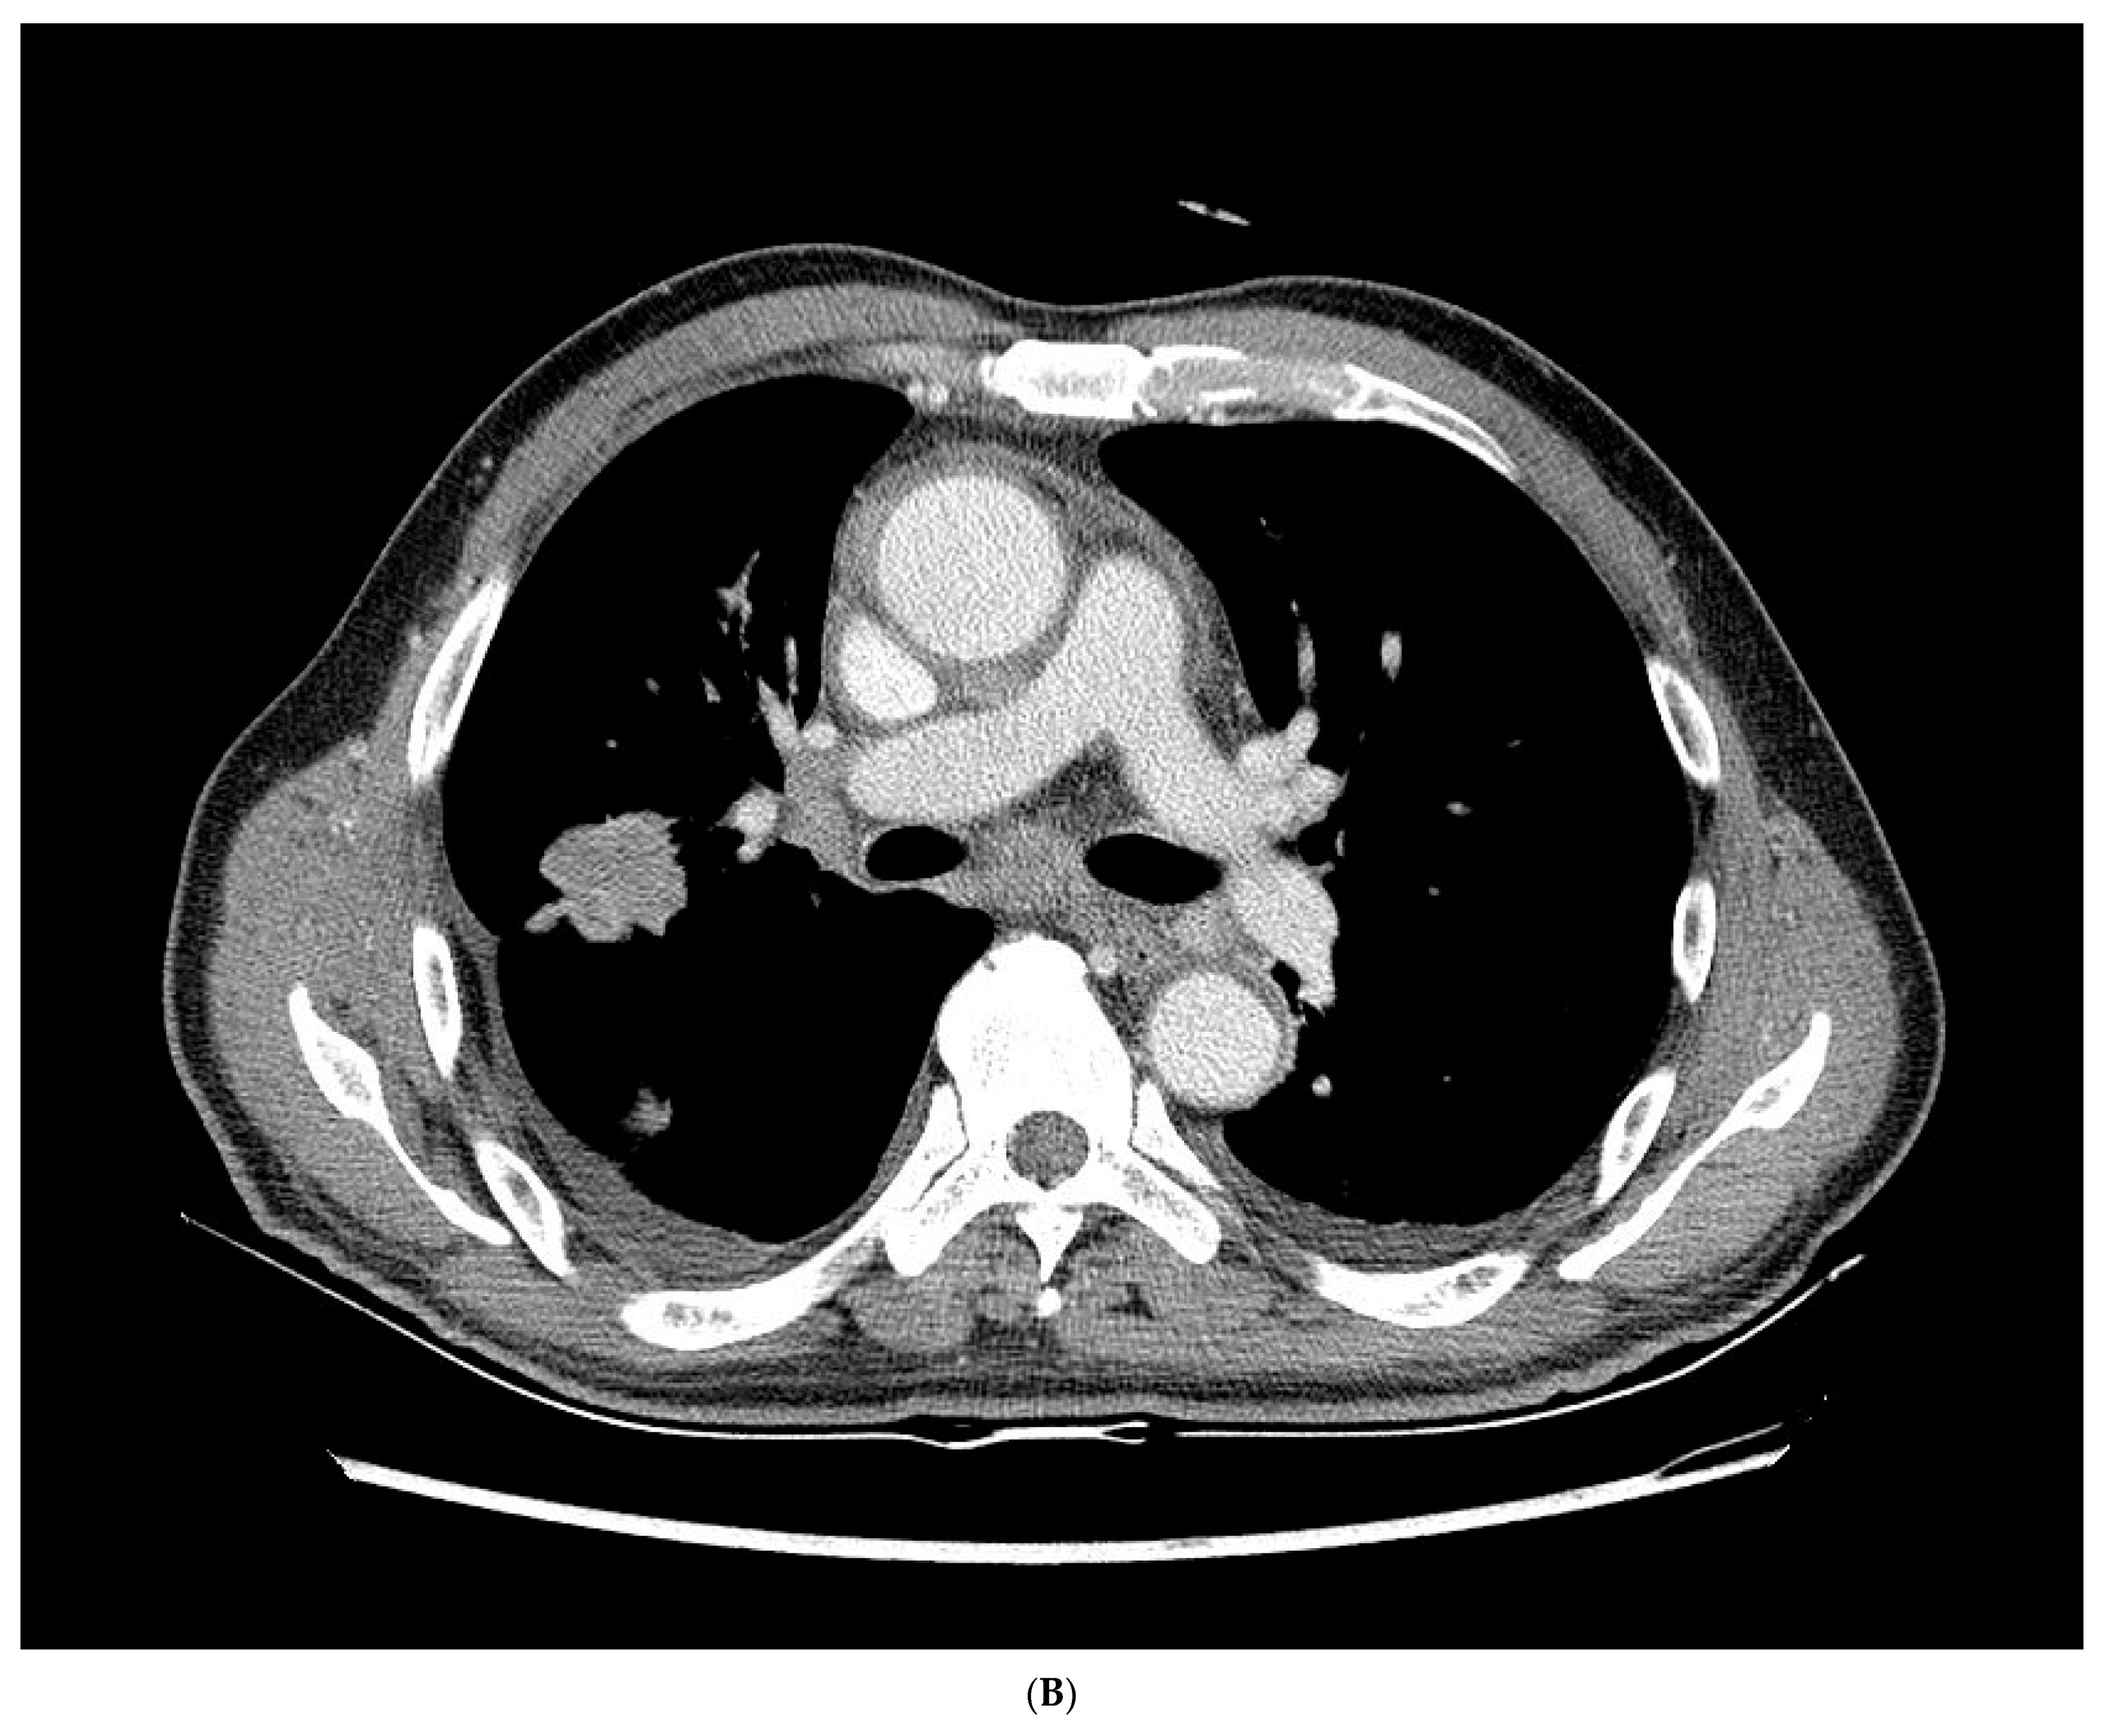

2. Case Report